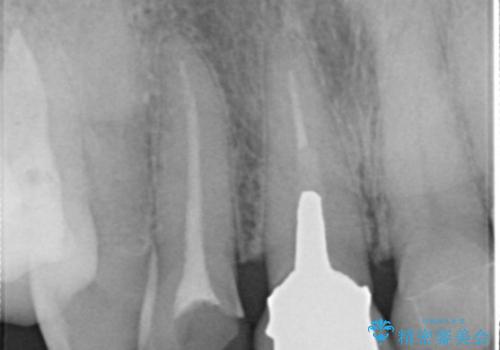

- 右上2番の審美性改善を主訴に来院された患者様です。

切削量と前歯ということからオールセラミッククラウンでの治療を選択しました。